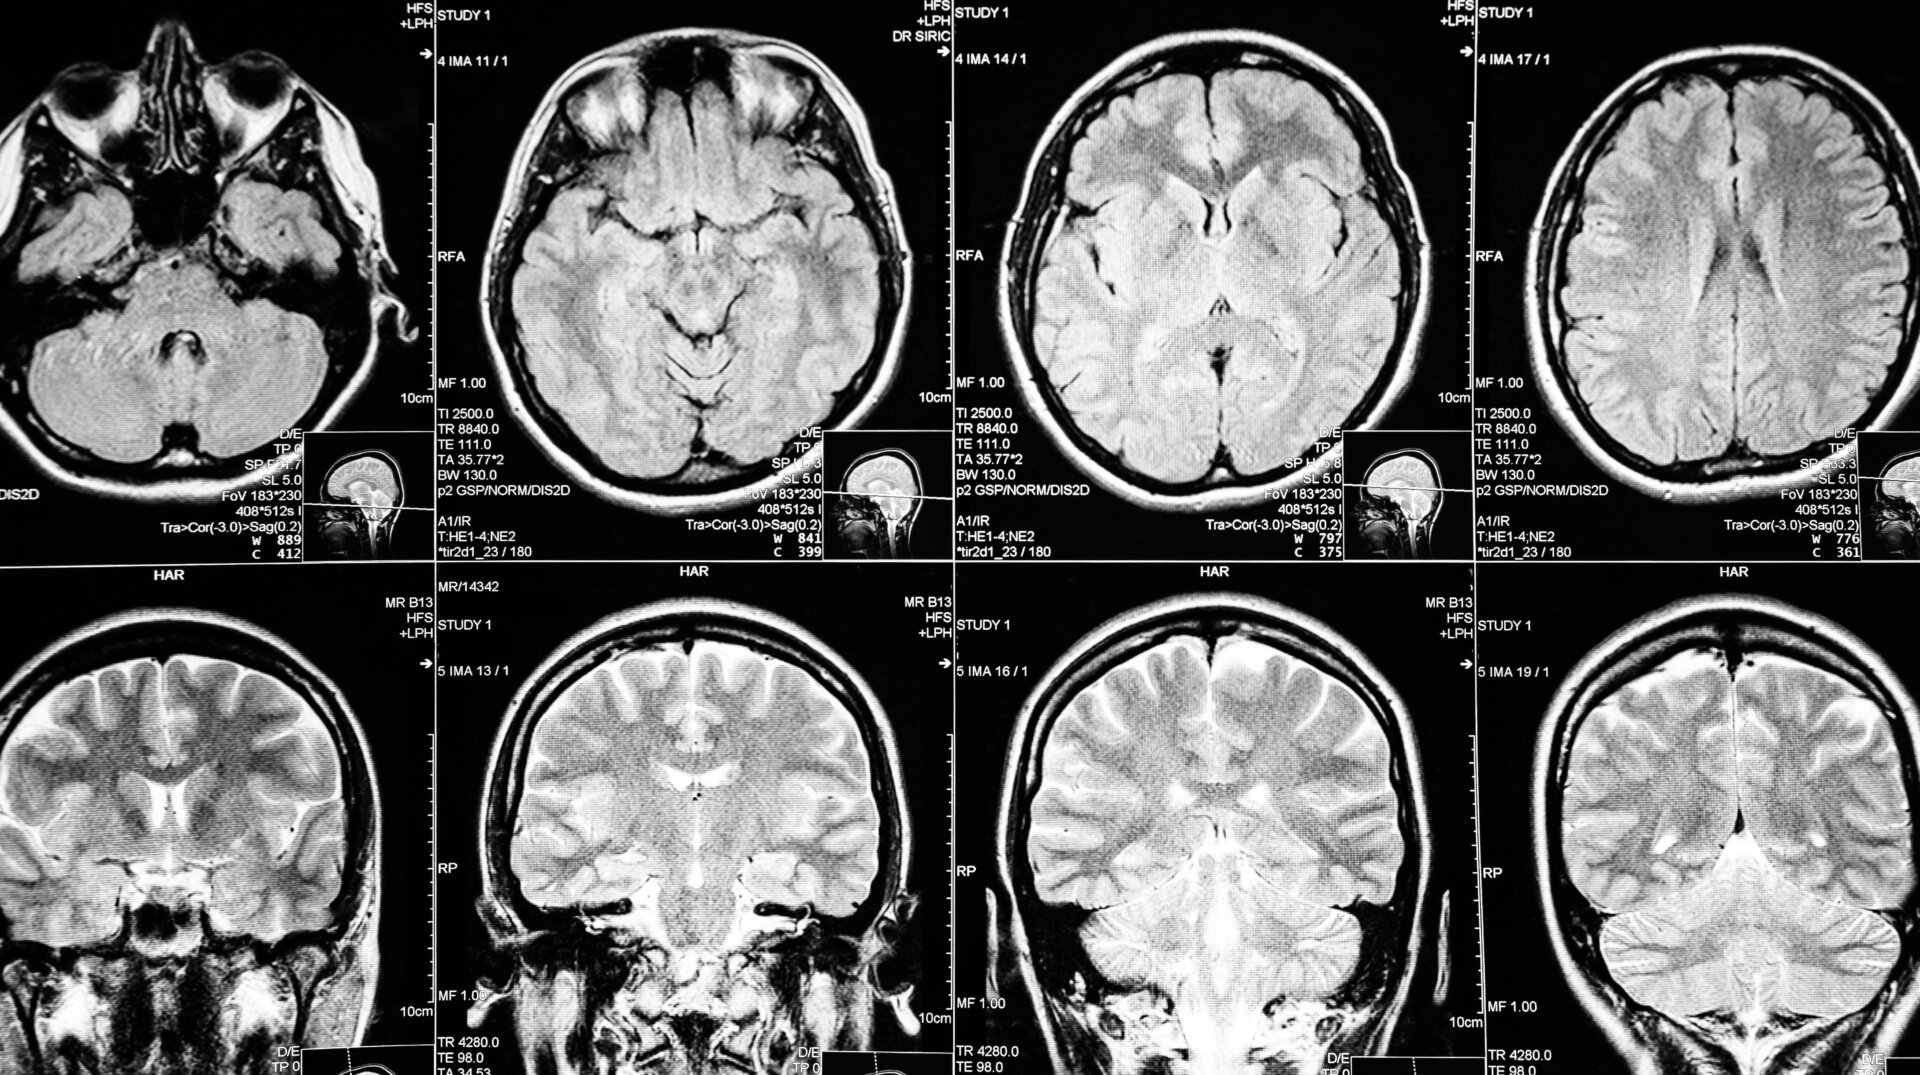

Lecanemab works by targeting amyloid beta, a protein naturally found in the body that’s thought to be a driving force behind Alzheimer’s, the most common form of dementia. In sufferers, a misfolded form of amyloid builds up in the brain over time, leading to the accumulation of hardy clumps called plaques. By breaking down or preventing these plaques from forming, the theory goes, you can slow or reverse the progression of Alzheimer’s, which is ultimately fatal.

The pivotal clinical trial that led to the FDA’s approval involved nearly 1,800 patients diagnosed with early Alzheimer’s. It found that patients taking lecanemab experienced a 27% slower loss in cognitive function over an 18-month period compared to the placebo group. Patients also appeared to have less amyloid plaque in their brains. The findings were revealed by the companies last September and were published in the New England Journal of Medicine in late November.